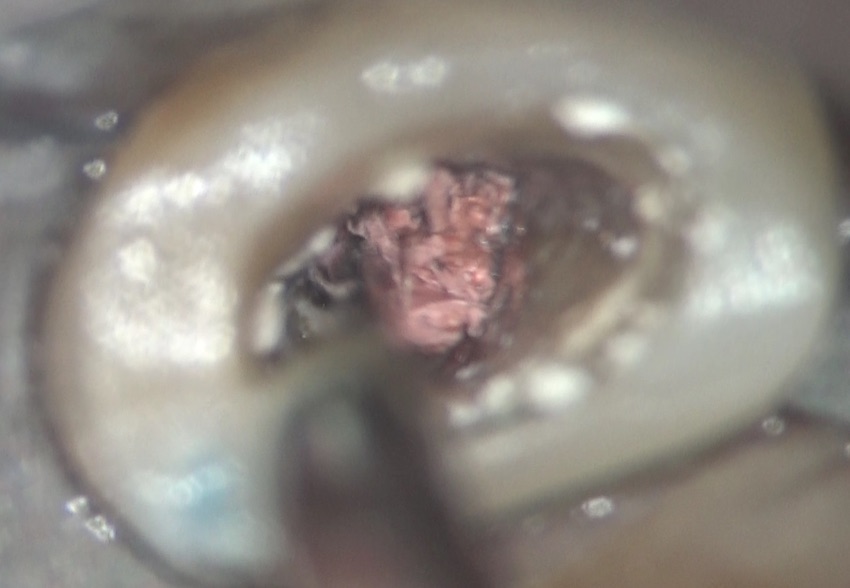

その綿を取り除くと、一般的に使用するガッタパーチャポイントが入っていて、その周囲には炎症性の体液と思われる液体が存在していました。

これらを取り除き、可能な限り、内部の細菌感染を除去していきました。